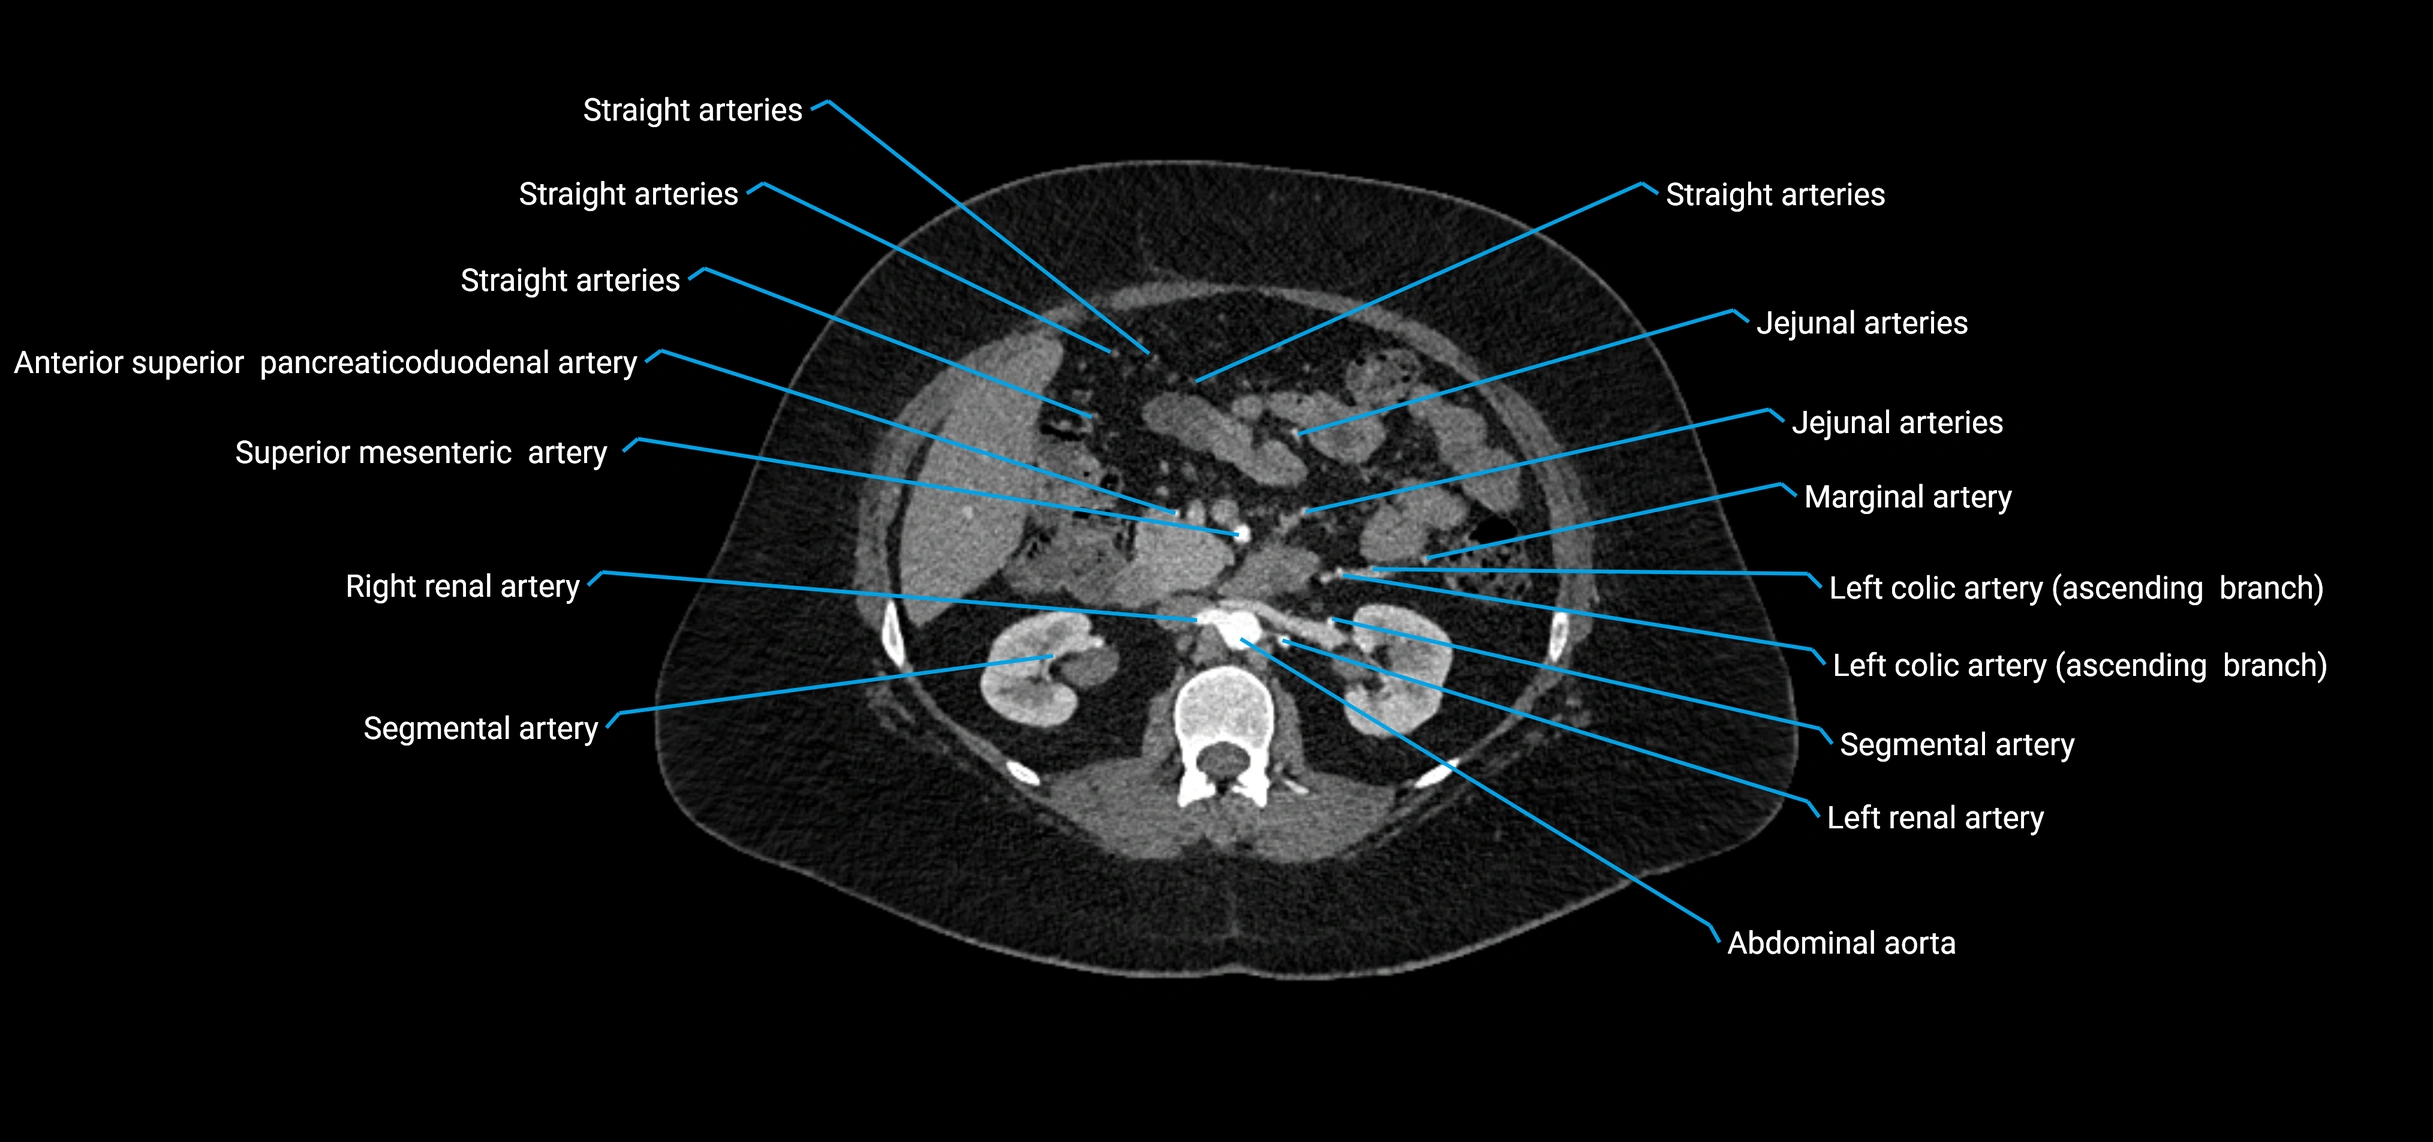

Contrast-enhanced CT (CTA):

• Gold standard for abdominal aortic imaging

• Provides excellent detail of lumen, wall, aneurysm, thrombus, and branch vessels

• Multiplanar and 3D reconstructions help in aneurysm measurement, stent graft planning, and dissection evaluation

• Detects acute rupture, traumatic injury, or occlusion with high sensitivity